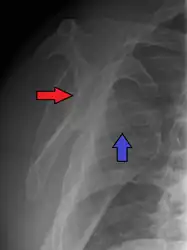

Posterior dislocations are uncommon, and are typically due to the muscle contraction from electric shock or seizure.[5] They may be caused by strength imbalance of the rotator cuff muscles. People with dislocated shoulders typically present holding their arm internally rotated and adducted, and exhibiting flattening of the anterior shoulder with a prominent coracoid process.

Posterior dislocations may go unrecognized, especially in an elderly person[11] and in people who are in the state of unconscious trauma.[12] An average interval of 1 year was noted between injury and diagnosis in a series of 40 people.[13]

Lightbulb sign indicative of posterior shoulder dislocation shown on the left. On the right, the same shoulder after reduction.

Axillary view of the left shoulder showing a posterior dislocation